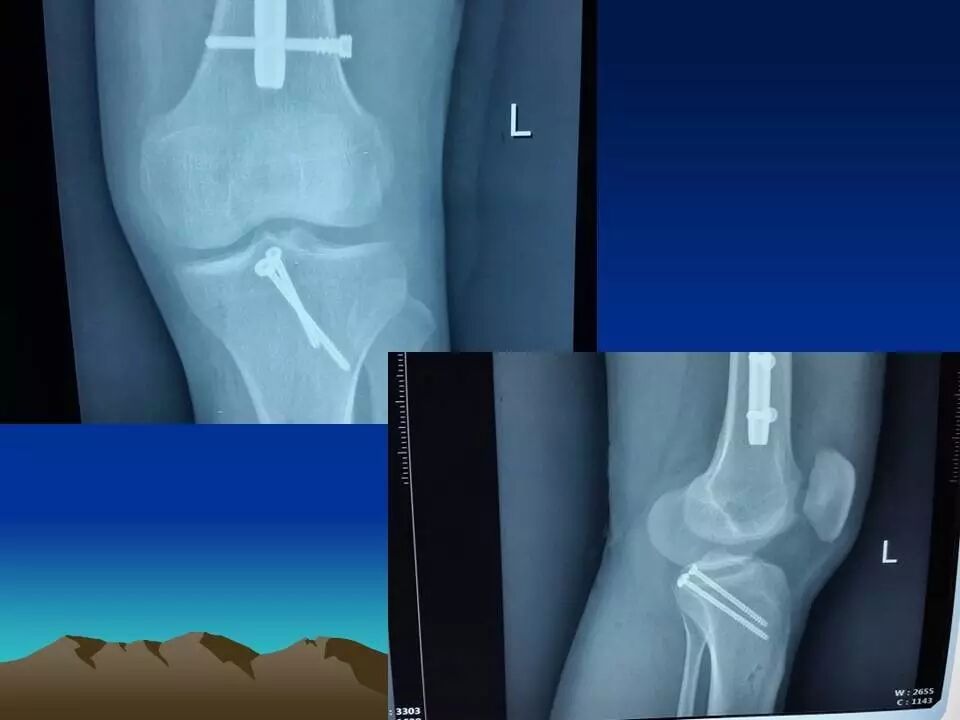

前十字韧带是膝关节重要的前向稳定结构,断裂后可以产生明显的膝关节不稳,严重影响膝关节功能,如果不及时治疗,关节出现反复扭伤,容易引起关节软骨、半月板等重要结构的损害,导致关节过早老化和骨关节病的发生。